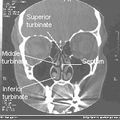

يعتبر الجدار الوحشي أكثر جدران جوف الأنف تعقيداً؛ إذ يساهم في تركيبه كل من العظم الأنفي والغربالي والدمعي والفكي العلوي والصفيحة العمودية للعظم الحنكي والصفيحة الجناحية الأنسية للعظم الوتدي. يتميز الجدار الوحشي ببروز ثلاث تراكيب عظمية تتوضع فوق بعضها تدعى المحارات الأنفية.[1][6] كما يتميز الجدار الوحشي بوجود ارتفاع دائري ينتج عن بروز الخلايا الغربالية المتوسطة نحو الأنسي يدعى الفقاعة الغربالية، وإلى الأسفل والأمام من هذه الفقاعة يوجد ثلم متقوس يدعى الفرجة الهلالية.[6]

يقسم جوف الأنف بواسطة حاجز الأنف إلى قسمين أيمن وأيسر، ويقسم كل منهما بواسطة المحارات الأنفية الثلاثة إلى أربع فسحات هي من الأعلى للأسفل:

- الردب الوتدي الغربالي: يقع فوق المحارة الأنفية العلوية وخلفها.

- الصماخ الأنفي العلوي: يقع تحت المحارة العلوية ووحشيها.

- الصماخ الأنفي الأوسط: يقع تحت المحارة الأنفية الوسطى ووحشيها.

- الصماخ الأنفي السفلي: يقع تحت المحارة الأنفية السفلية ووحشيها.[1]